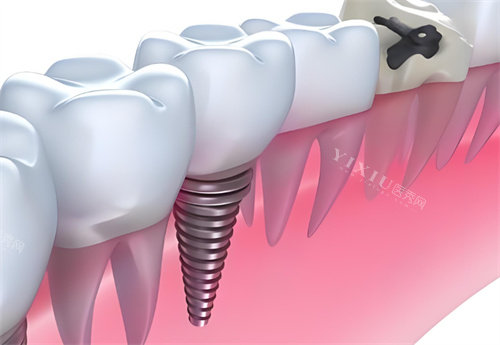

CDIC种植体采用四级纯钛作为基础材料,这种材质在生物相容性方面表现良好。其表面处理技术采用大颗粒喷砂加酸蚀工艺,这种处理方式能够提供较好的骨结合能力,有利于种植体与颌骨的整合。

然而从制造工艺角度看,CDIC的加工复杂度和精细程度与高端品牌产品相比有所不足。这主要体现在螺纹设计、连接结构等细节方面,这些因素可能影响长期使用的稳定性。